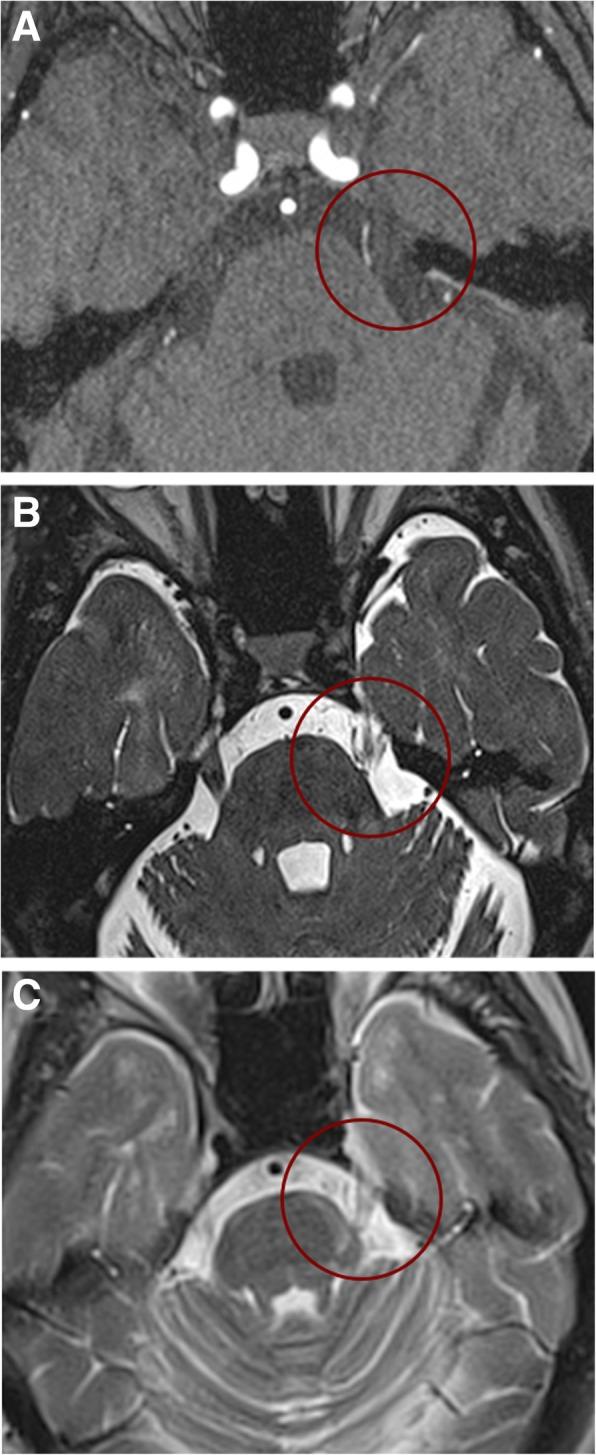

Trigeminal neuralgia secondary to multiple sclerosis manifests with facial paroxysmal pain triggered by typical manoeuvres; neurophysiological investigations and MRI support the diagnosis, providing the definite evidence of trigeminal pathway damage. A dedicated MRI is required to identify pontine demyelinating plaques. In many patients with multiple sclerosis, neuroimaging and surgical evidence suggests that neurovascular compression might act in concert with the pontine plaque through a double-crush mechanism. Although no placebo-controlled trials have been conducted in these patients, according to expert opinion the first-line therapy for trigeminal neuralgia secondary to multiple sclerosis relies on sodium-channel blockers, i.e. carbamazepine and oxcarbazepine. The sedative and motor side effects of these drugs frequently warrant an early consideration for neurosurgery. Surgical procedures include Gasserian ganglion percutaneous techniques, gamma knife radiosurgery and microvascular decompression in the posterior fossa.

多发性硬化症继发的三叉神经痛表现为面部阵发性疼痛,由典型动作触发;神经生理研究和 MRI 支持诊断,提供三叉神经通路损伤的确切证据。需要专门的 MRI 来识别桥脑脱髓鞘斑块。在许多多发性硬化症患者中,神经影像学和手术证据表明,神经血管压迫可能通过双重挤压机制与桥脑斑块协同作用。尽管这些患者没有进行安慰剂对照试验,但根据专家意见,多发性硬化症继发三叉神经痛的一线治疗依赖于钠通道阻滞剂,即卡马西平和奥卡西平。这些药物的镇静和运动副作用常常需要早期考虑神经外科治疗。手术包括经皮三叉神经节技术、伽玛刀放射外科和后颅窝微血管减压术。